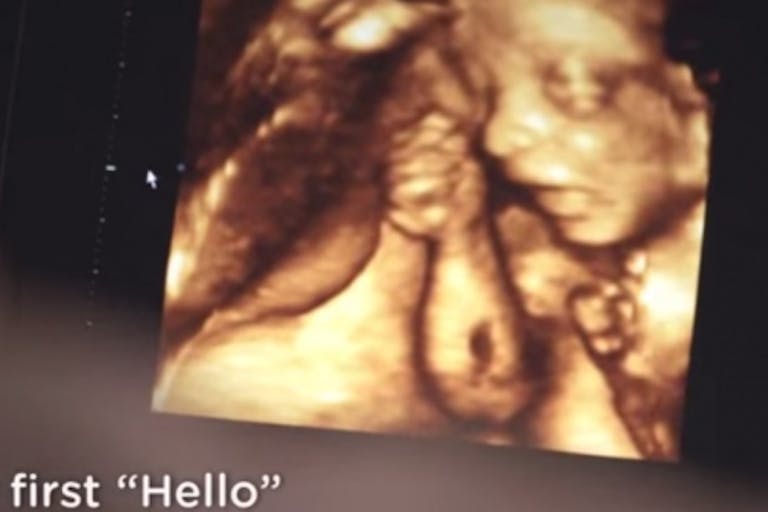

This time, Pampers’s ad — which has already received over 860,000 views on YouTube — opens as a mother lovingly caresses her pregnant belly. The scene switches to an incredible ultrasound where a baby is moving in the womb and, as Pampers puts it, is giving her “first hello.”

From the first scan to the first cuddle, every first is significant no matter how small they seem. For both baby and mom, it’s a journey full of firsts. And there’s nothing more rewarding than experiencing each and every one together.